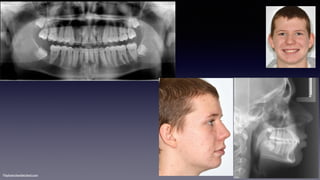

•Class II div 2

MaHe220611

Class II div 1

NaPa081105

•Class II div 1

•Missing 17, 26, 35, 45

KeBiDu080609